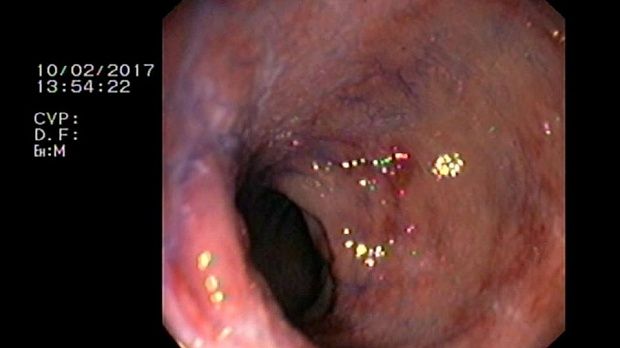

2 мл ( это мин сум, а мы делаем до 10 мл 3% перекись+200 мл физ раствора